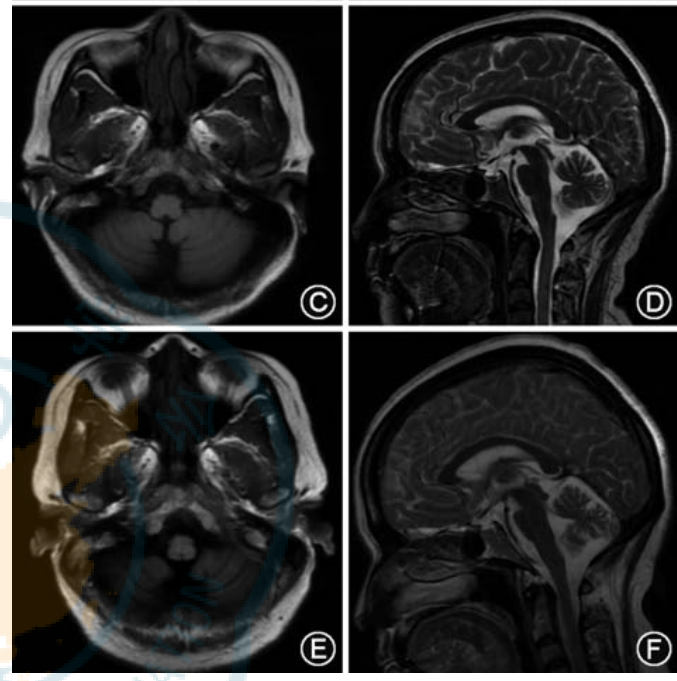

♦ 疾病进展期的MRI表现

随着ACA的进展,头颅MRI可能揭示以下变化:

小脑萎缩:小脑体积减小,反映了疾病的慢性进展。

代谢减低:PET-CT可能显示小脑代谢活动的降低。

患者 3:病程 16个月时,头颅 MRI示小脑及脑干

大致正常(C、D);病程32个月时,头颅MRI示小脑脑干萎缩(E、 F)

♦ 后遗症期的特殊表现

小脑明显萎缩:伴随脑桥“十字面包征”,这是一种特征性的神经影像学表现(图 2C~F)。